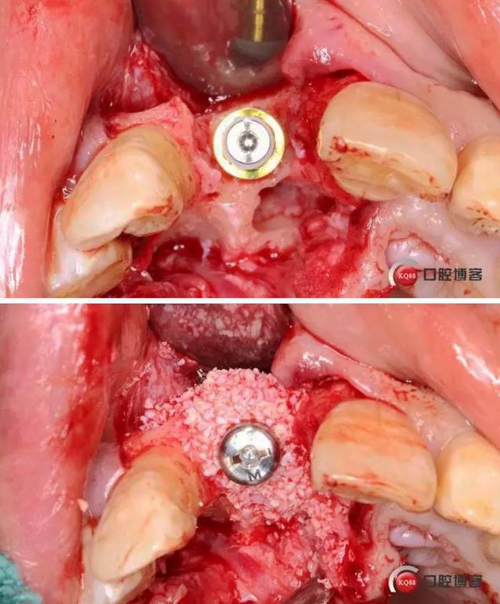

術(shù)中照

術(shù)后縫合